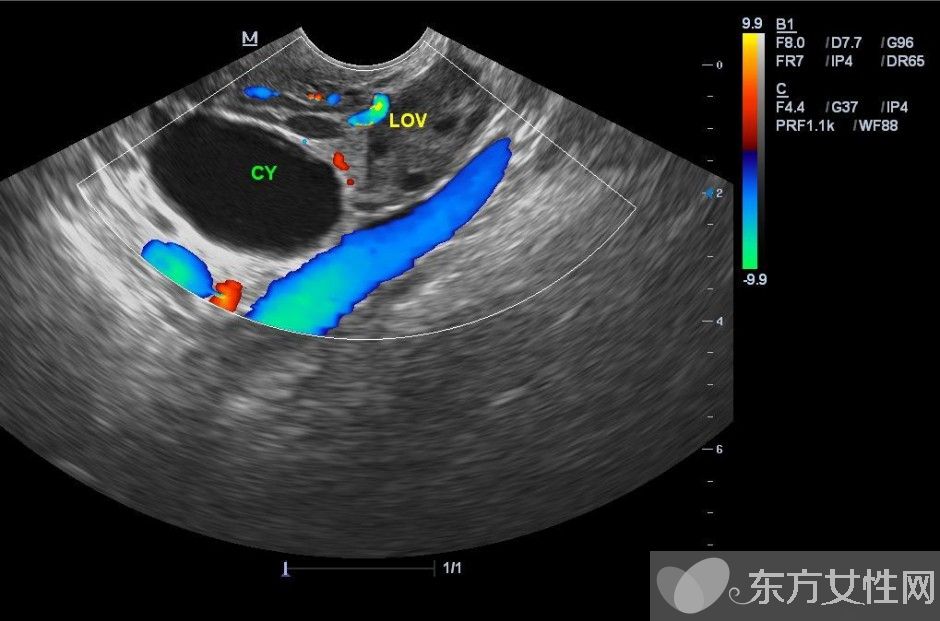

什么是卵巢囊肿?

卵巢囊肿是指卵巢上长出的囊性肿物,有各种不同的性质和形态,如单一型或混合型、一侧性或双侧性、囊性或实质性、良性或恶性。通常可分为两大类:

卵巢囊肿分为生理性和病理性两种,卵巢囊肿的症状有哪些?生理性的卵巢囊肿是在女性排卵期滤泡聚集而形成的,往往几个月后会自动消失。病理性的卵巢囊肿在早期也没有明显的症状,有症状者多表现为腹部疼痛、月经不调、白带异常、腹部肿块等,容易被忽视或误诊。

如果是单纯性囊肿,没有分隔,没有囊内乳头,没有钙化等复杂的特征,基本上是良性,可以保守观察。4-8周后复查时囊肿通常会变小或者消失。如果囊肿不消失,但是超声显示仍是单纯性囊肿,仍然可以继续严密观察。卵巢生理性囊肿如合并月经紊乱等内分泌症状者,可口服药物治疗以减轻症状,但对于病理性囊肿,目前还没发现有明确疗效的口服药物。